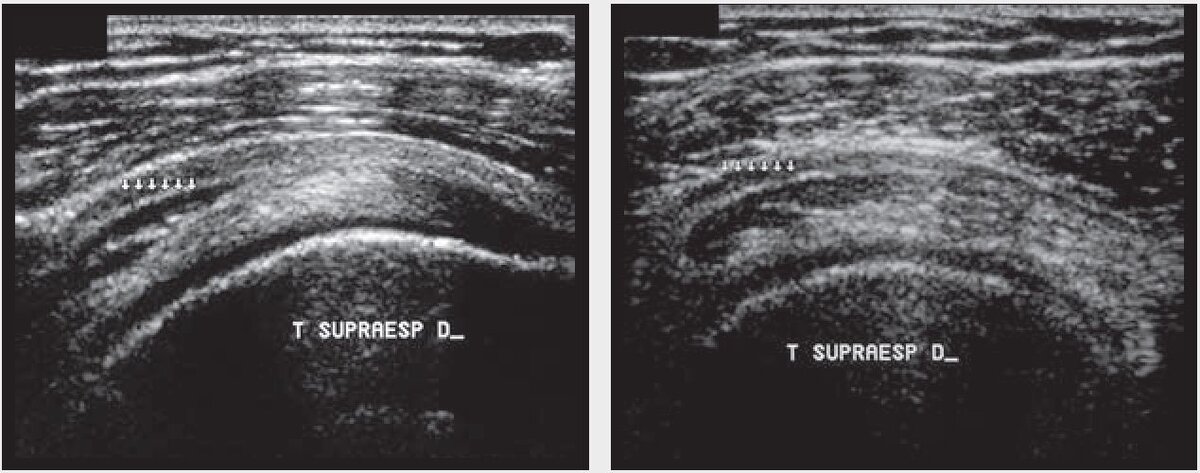

Введение мышечных волокон внутрь сухожилия можно проиллюстрировать на примере вращательной манжеты плеча (рис. 2). В некоторых мышечно-сухожильных узлах более одного мышечного волокна вносят свой вклад в структуру сухожилия. Надлопаточное сухожилие (supraspinatus) состоит из пяти слоев, один из которых представлен переплетением его волокон с волокнами инфраспинатусного сухожилия (рис. 3). На энтезисе сухожилие изменяет свою гистологию в месте вхождения в кость и представляет собой фиброхрящ, эхогенность которого на УЗИ низкая (рис. 4).

Рис. 3. Нормальная гетерогенность надлопаточного сухожилия из-за различной пространственной ориентации слоев сухожилия, создающая трехполосный аспект (звезды)